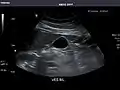

Liver

Ultrasonography of the liver with some standard measurements[6]

In patients with deranged liver function tests, ultrasound may show increased liver size (hepatomegaly), increased reflectiveness (which might, for example, indicate cholestasis), gallbladder or bile duct diseases, or a tumor in the liver.

Ultrasonography of liver tumors involves two stages: detection and characterization. Tumor detection is based on the performance of the method and should include morphometric information (three axes dimensions, volume) and topographic information (number, location specifying liver segment and lobe/lobes). The specification of these data is important for staging liver tumors and prognosis. Tumor characterization is a complex process based on a sum of criteria leading towards tumor nature definition. Often, other diagnostic procedures, especially interventional ones, are no longer necessary. Tumor characterization using the ultrasound method will be based on the following elements: consistency (solid, liquid, mixed), echogenicity, structure appearance (homogeneous or heterogeneous), delineation from adjacent liver parenchyma (capsular, imprecise), elasticity, posterior acoustic enhancement effect, the relation with neighboring organs or structures (displacement, invasion), vasculature (presence and characteristics on Doppler ultrasonography and contrast-enhanced ultrasound (CEUS).